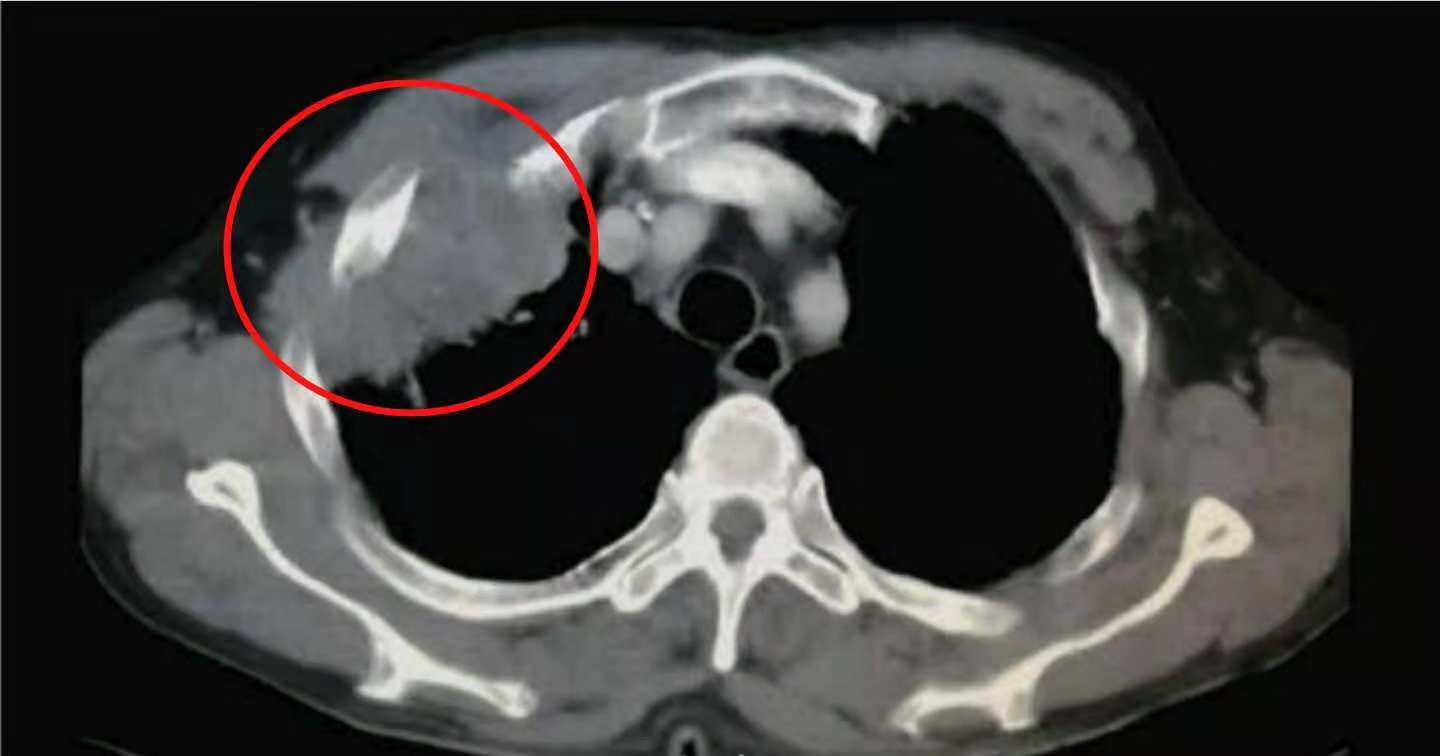

上图这位老人,在72岁的时候发现左侧早期肺癌,觉得年纪大了,没有选择手术也没有采用其他任何治疗。

11年后,老人83岁的时候最后一次来复查,肿瘤已经进展到晚期:

之后就失去联系了。